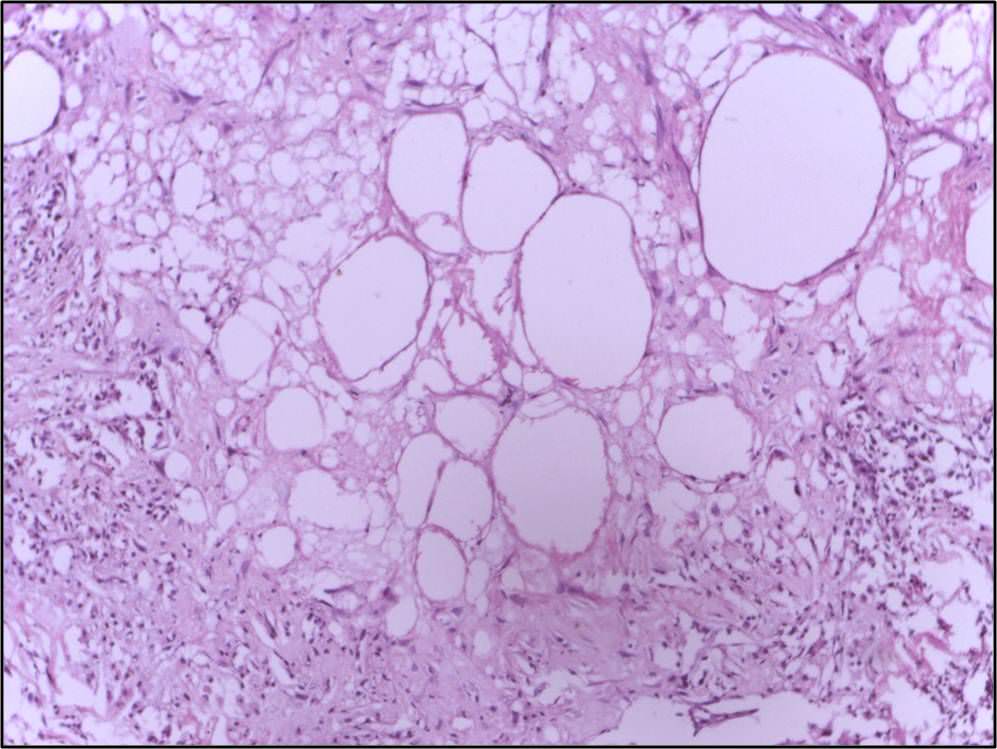

FileTryptic fat tissue necrosis in severe pancreatitis, HE 2.jpg wikidoc What Is Compression Necrosis Compression necrosis refers to bone tissue damage that can occur when excessive pressure or force is applied to surrounding bone. The most effective treatment to reduce oedema in mobile patients is compression, which is also true for patients with compensated cardiac oedema and in patients with concomitant arterial occlusive disease in which positive 60 Surrounding bone during implant placement. The. What Is Compression Necrosis.